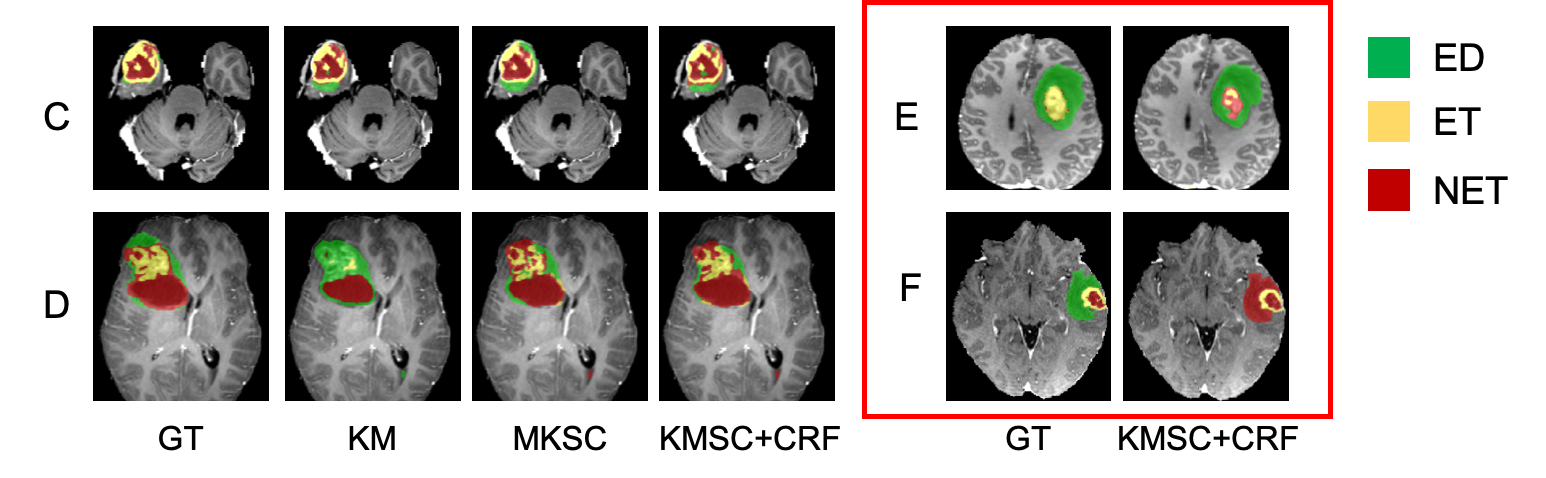

Refer to caption

Figure 2: Results of two sample slices (A and B) on different settings in phase1. GT: ground truth. Dice scores are reported. Yellow arrow: false negative area. Blue arrow: false positive area.

It is shown in Table 1 that our weakly supervised model (SC+GC+CRF) for WT can achieve competitive result that is very close to the fully supervised model with only a 1.64% margin. Graph Cut is very effective (SC+CRF v.s. SC+GC+CRF) by providing more correct labeled samples to Unet-WT, as shown in Table 1 as well as in Fig. 1. In addition, finetuning the model with CRF loss efficiently improves the model, which boosts the WT Dice score by 3%similar-toabsentpercent3\sim 3\% compared with the SC+GC setting. As shown in Fig. 2, CRF loss offers substantial advantages in delineating the tumor boundaries. Fig. 2 shows some negative area in sample B (SC+GC+CRF), that is caused by a strong edge inside the tumor because of the CRF loss.